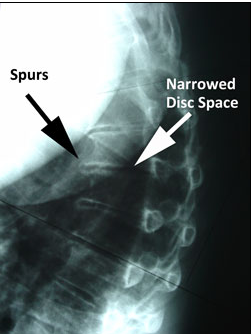

퇴행성 변화

- 척추체 앞쪽의 돌출부, 골극(검은색 화살표)

- 디스크 퇴행을 나타내는 좁아진 공간(흰색 화살표)